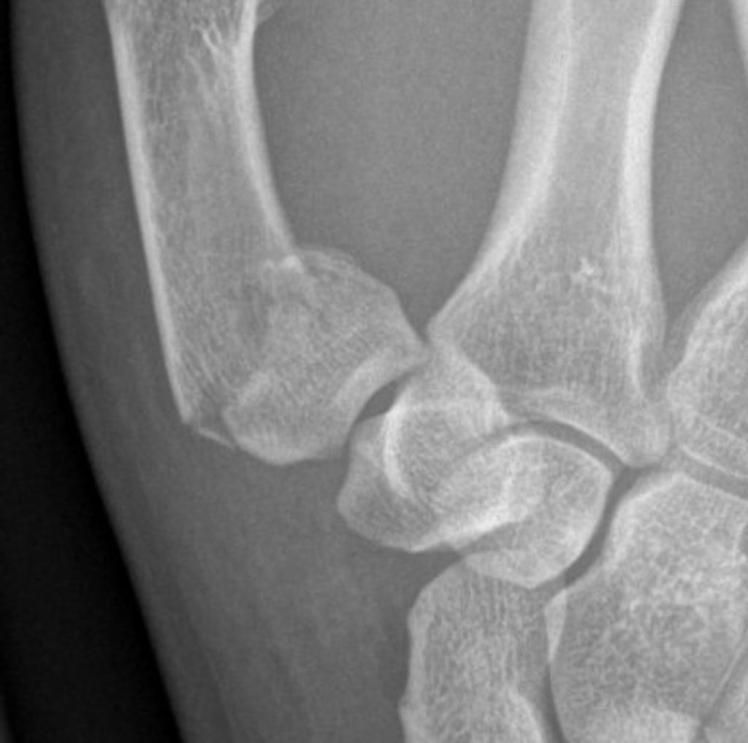

17yo male who punched someone’s face. What is this thumb injury called? Gepost op 21 september 201721 september 2017 door netwerkvsseh What is this thumb injury called? @radiopaedia.org Dit delen: Delen op X (Opent in een nieuw venster) X Share op Facebook (Opent in een nieuw venster) Facebook Delen op LinkedIn (Opent in een nieuw venster) LinkedIn E-mail een link naar een vriend (Opent in een nieuw venster) E-mail Afdrukken (Opent in een nieuw venster) Print Vind-ik-leuk Aan het laden... Gerelateerd